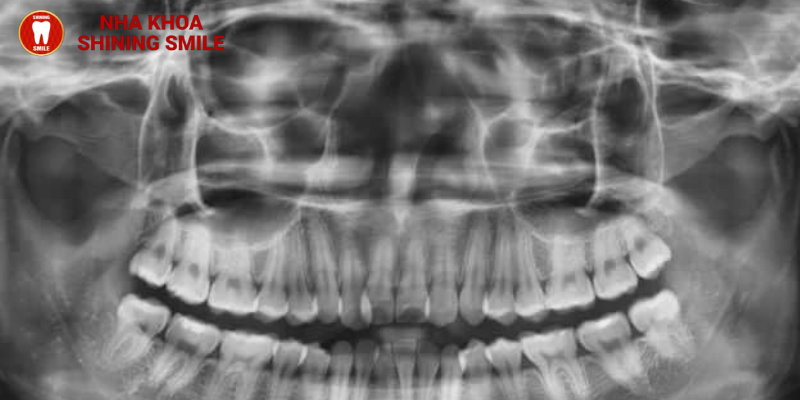

Trong một số trường hợp nhất định, để răng có khoảng cách để di chuyển và việc niềng răng đạt hiệu quả cao nhất thì việc nhổ răng sẽ trở nên cần thiết. Tuy nhiên, không phải ai niềng răng cũng cần nhổ răng mà chỉ được bác sĩ cân nhắc kỹ lưỡng và đưa ra chỉ định nhổ răng để phù hợp với kế hoạch điều trị tại thời điểm đó. Hãy cùng SHINING SMILE tìm hiểu chi tiết tại đây